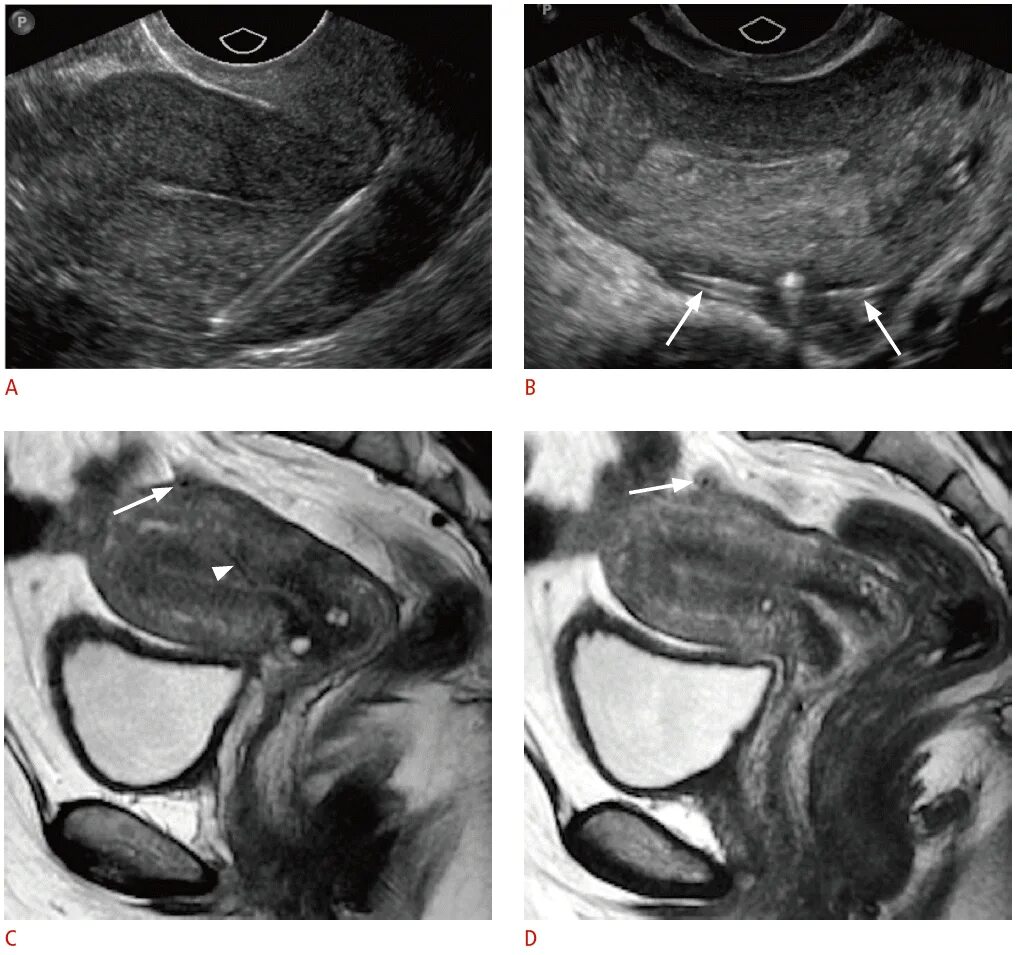

Вмс шейки матки